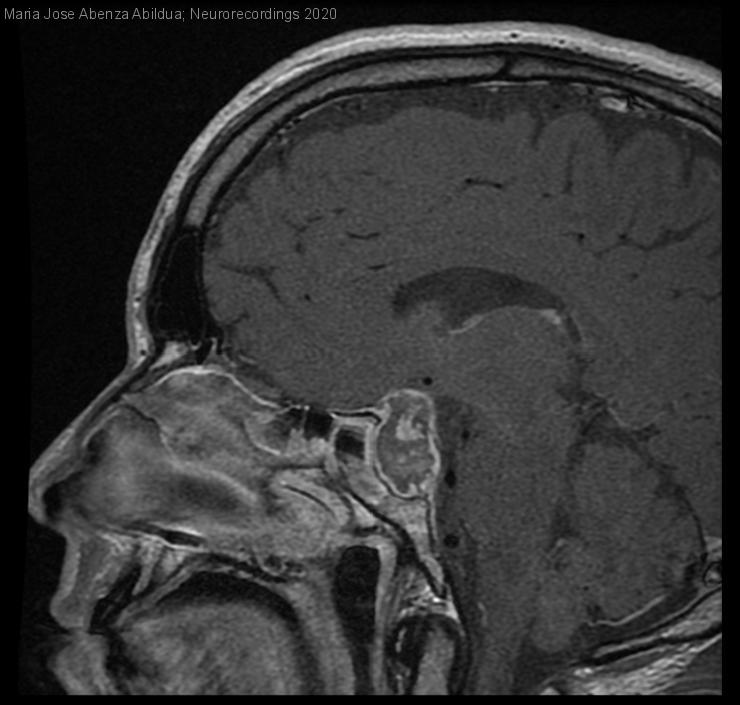

Apoplejía hipofisaria

Hombre | 47 años

Diagnóstico final: Apoplejía hipofisaria

Varón de 47 años, sin antecedentes, que acude a Urgencias por cefalea brusca frontal opresiva de 36 horas de evolución, de inicio nocturno, con naúseas, vómitos, foto y sonofobia, se irradia hacia región temporal bilateral, sin...